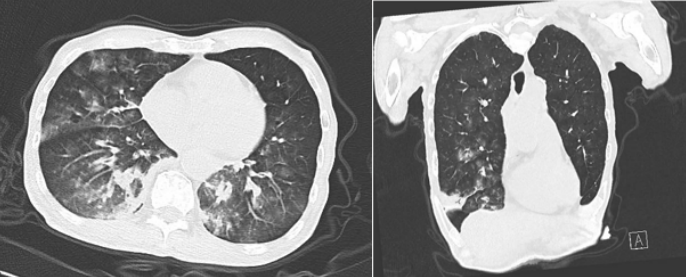

患者,男性,81岁,鼻骨骨折后呛咳4 d,因呼吸困难而入院。Tmax 39.2℃(图1),WBC 7.25×109/L,NEU% 85.5%。既往诊断2型糖尿病10年、帕金森病6年。入院一段时间后,BALF及痰培养结果均显示“肺炎克雷伯菌”。患者胸部CT也符合肺炎克雷伯菌感染特征(图2)。